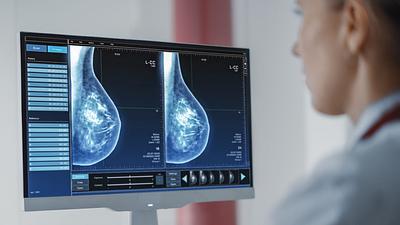

Escassez de mamógrafos dificulta prevenção do câncer de mama

O Brasil tem uma cobertura muito baixa de mamografias: 24%. O ideal recomendado pela Organização Mundial da Saúde é de 70%.